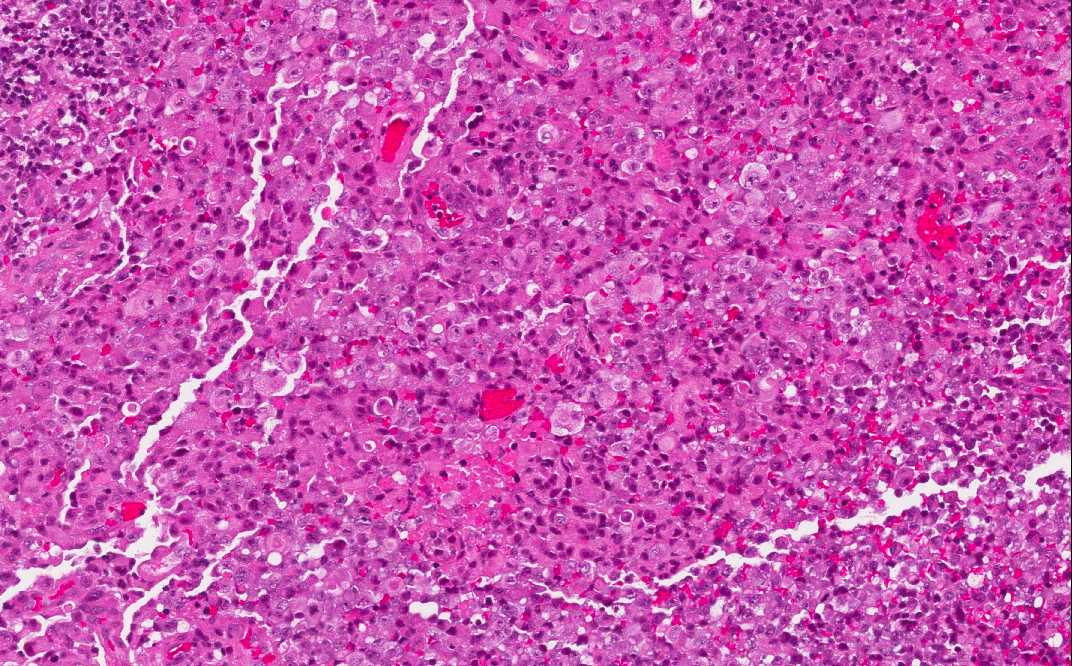

Hematoxylin & eosin

Intraoperative frozen section: The rhabdoid features of the tumor cells are readily seen at the time of intraoperative crozen section. This part of the specimen has more necrosis than the part submitted for permanent section.

• The tumor is composed of solid sheets of moderate to large cells with large nuclei and prominent nucleoli (Area 1). There is no specific pattern formation. The tumor cells tend to separate from each other. There is some small focal necrosis in this section but the necrosis is more extensive in the part submitted for frozen section (see bonus images below).

• Note that there is significant variation in the size of the cells. Some of them are rather large and has eccentrically located nuclei and big "belly" of cytoplasm.